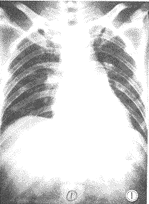

①肺纹理增粗增浓,血管影像模糊,伴有广泛的斑点状或小片状影像,密度较淡,边缘模糊。本组有27例,占34.6%(图1)。

图1 间质型:显示肺纹理增粗模糊,伴有斑点状及小片状阴影形成。